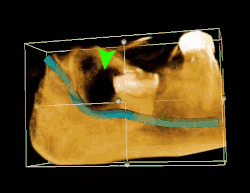

| 3D CT of an impacted wisdom tooth adjacent the inferior alveolar nerve prior to removal of wisdom tooth | |